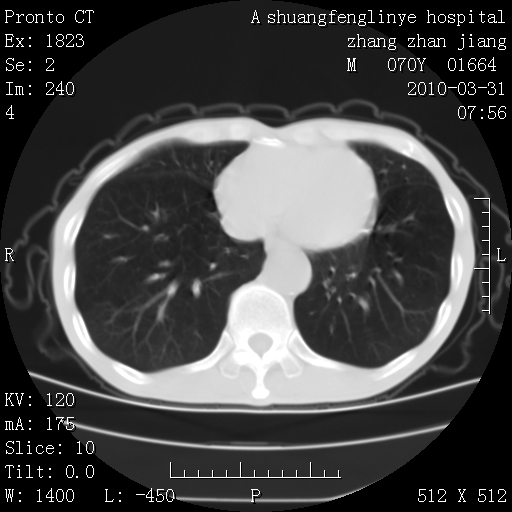

双上肺继发型tb并左上空洞形成,主动脉冠脉钙化。

1)两肺上叶继发性肺结核并左肺上叶空洞形成。2)冠状动脉及主动脉钙化。